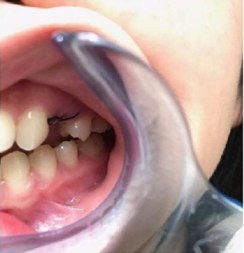

下图是我带上牙套后的样子,基本上是看不出来的,可以说是非常隐形了!

其实还有20个牙套,但是我的凸牙已经基本上都回去了,改变巨大。下面放羞羞的真人图。